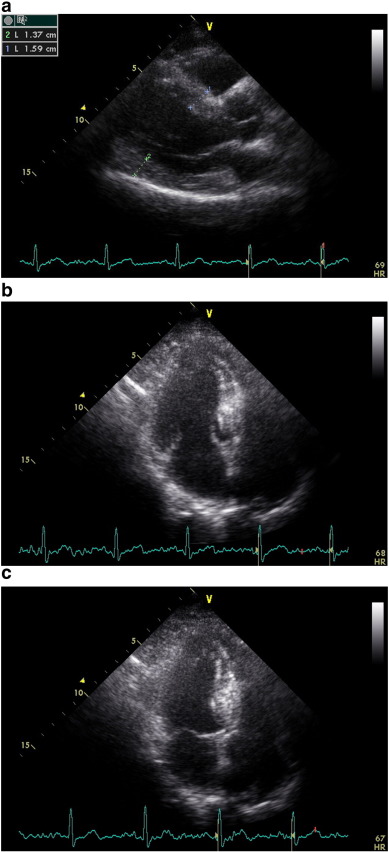

Evaluation of isovolumetric contraction time, contraction time and isovolumetric ...

Fig. 1.

Evaluation of isovolumetric contraction time, contraction time and isovolumetric relaxation time of the LV septal base by tissue Doppler imaging in a hypertensive patient (MPI = 51).

Demographic features of 3 groups were pointed out in Table 1. Two dimensional echocardiography was performed in all groups and there was no difference in global LV systolic function. There was no difference in heart rate and blood pressure between the groups during echocardiographic evaluation (Table 2). Mean ejection fraction was similar among the groups, while LV mass index was greater in group II compared with group I and group III (p < 0.0001), (Table 2). We determined thickened walls at parasternal long-axis view in the group II (Fig. 2a). The LV geometric pattern was detected as concentric hypertrophy in this group. (RWT: 0.49 ± 0.8, Table 2). In addition to thickened walls, before functional quantification of regional myocardial tissue using TDI in apical view, we observed LV cavity obliteration during systolic contraction in the patients with LVH (Fig. 2b, c) which is most likely related to thickened walls compared to the other groups.

a, b, c: End-diastolic parasternal long-axis view, apical LV cavity geometry ...

Fig. 2.

a, b, c: End-diastolic parasternal long-axis view, apical LV cavity geometry during diastole and end-systolic LV intracavitary obliteration by remarkable hypertrophied septal wall in an advanced hypertensive patient with left ventricular hypertrophy, respectively.